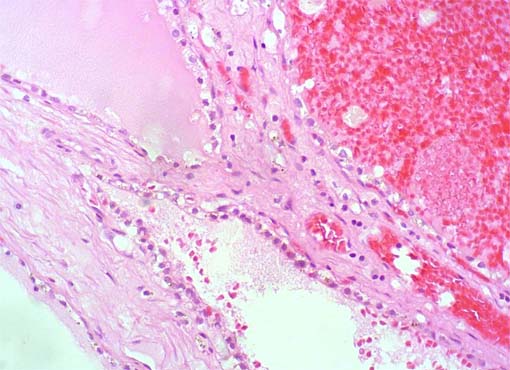

Figura 3.

H&E, X200.

No se encontraron áreas sólidas

con células claras ni había parénquima renal en los

septos.